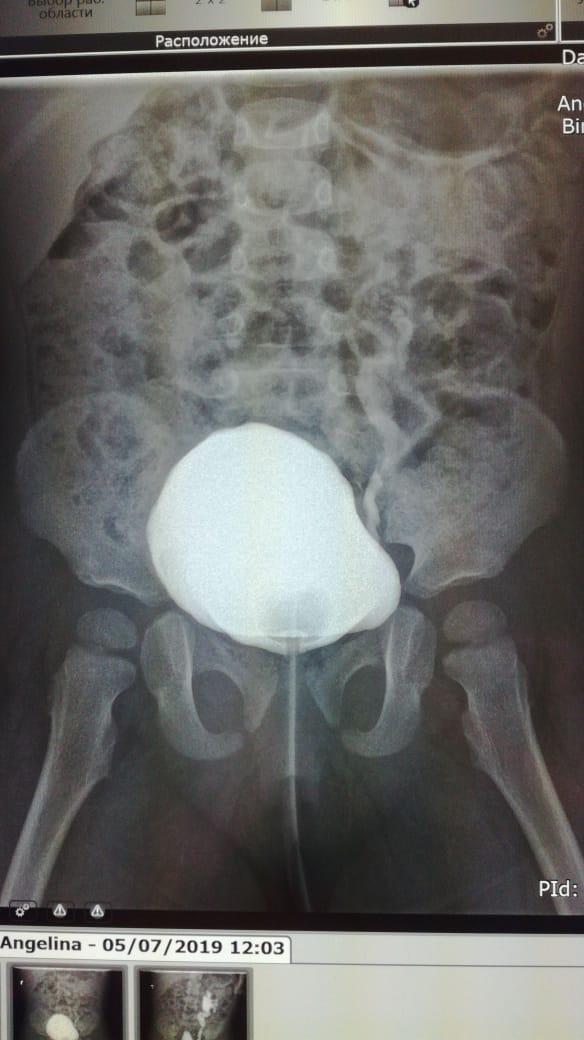

Здравствуйте.Ребенку 14.09.17г.р.сделали эндоскопическую коррекцию ПМР 4ст.второй раз ,хотя квота выписывалсь на сложную операцию.После коррекции ребенок стал мочиться еще реже и ухудшился ОАМ на четвертые сутки.